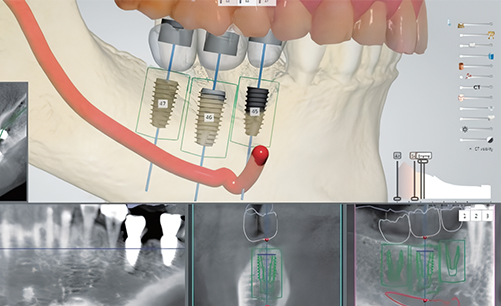

디지털 네비게이션 임플란트 진행

3D CT 데이터 기반으로 모의 수술을 진행하여

최적의 식립 위치를 계획합니다.

그 후 맞춤형 가이드를 제작하여

정확성 높은 임플란트를 식립합니다.

디지털 네비게이션 임플란트로 계획한 위치에 정확한 임플란트 식립이 가능합니다.